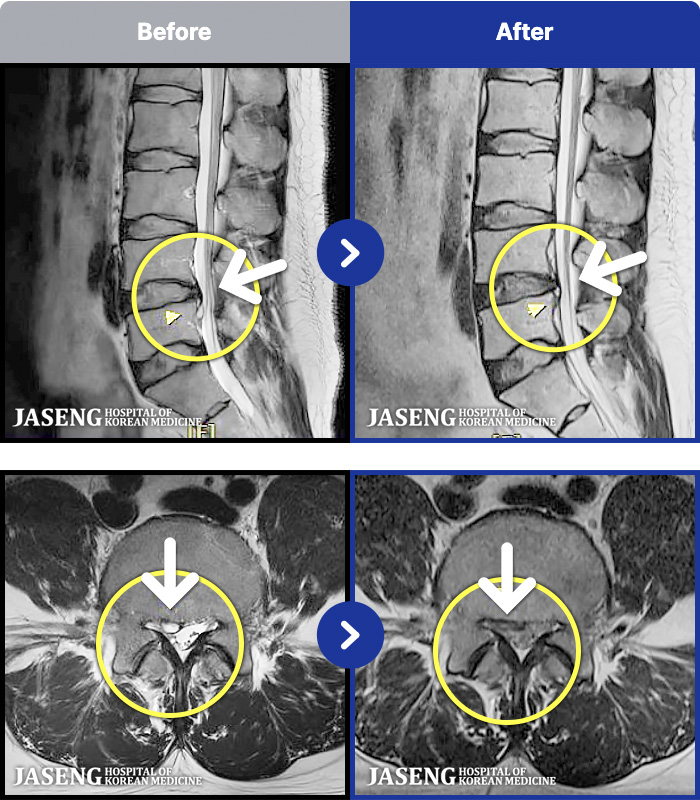

95 MRI ũ ʸ Ȯϼ.

[_㸮ũ] 㸮 , ̾ ȭǾ ϼ̽ϴ.

[_㸮ũ] 1 ʴ 㸮 , ̾ ɾҴ Ͼ ȭǾ ϼ̽ϴ.

[_㸮ũ] 㸮 кκ , ߸ ϼ̽ϴ.

[_㸮ũ] 㸮 ϰ , ٸ ̾ ϼ̽ϴ.

[_㸮ũ] 㸮 ݵǴ ְ, ɰų ȭǾ ϼ̽ϴ.

[_㸮ũ] 㸮 ϰ , ̾ ϼ̽ϴ.

[_㸮ũ] 㸮 , ٸ ̾ ϼ̽ϴ.

[_㸮ũ] 㸮 ߰ Ͽ ϼ̽ϴ.

[_㸮ũ] Ƹ ߱ ̾ ϼ̽ϴ.